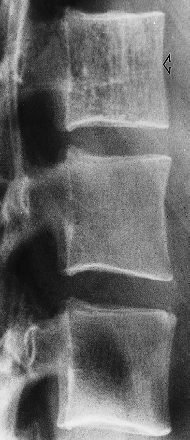

3- Paget’s disease:

This may be difficult to distinguish from neoplastic disease, but a useful diagnostic feature is expansion of the overall size of the vertebra with coarsening of the trabecular pattern in Paget’s disease. increased density and coarse trabeculae in the wider than the normal vertebral bodies (arrows)